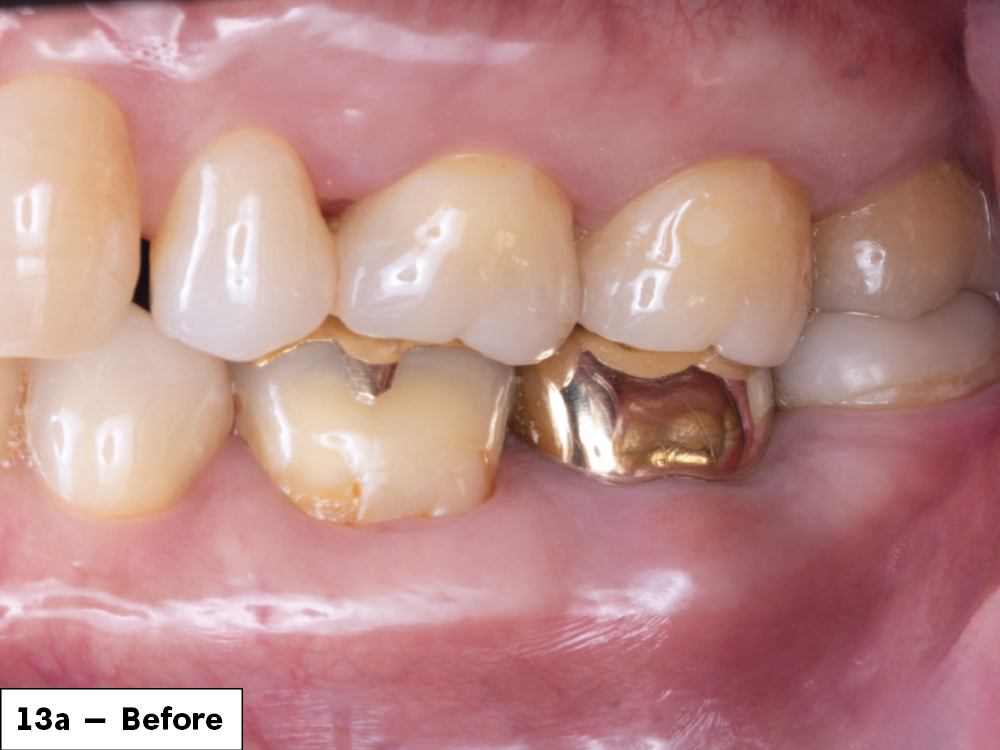

Before tooth surgery

1 year after tooth surgery

Figures 13a, 13b: One year after removing the tooth and infection, the final screw-retained crown demonstrated great stability and esthetics. The patient was happy with the restored functionality of his tooth.